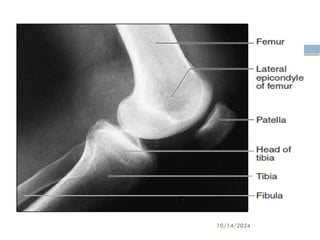

Thigh

 The is the longest, heaviest, strongest bone in the body.

 The distal end of the femur is expanded for

patella

Leg

Tibia

 The condyles are separated by a slight upward

 The medial malleolus is a prominent medial knob

Fibula